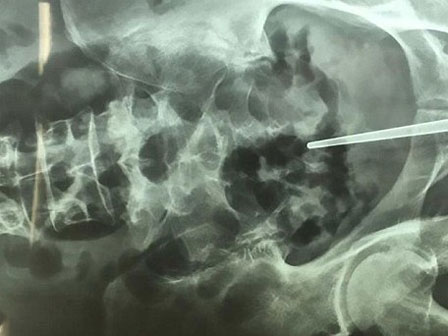

Trong quá trình cắt đai ốc kéo dài 94 phút, dù đã cố gắng khéo léo nhưng dương vật của người đàn ông này vẫn bị rách 2 miếng dài 1cm và 2cm. Mặc dù bị rách dương vật nhưng đai ốc kim loại đã được loại bỏ thành công, nhóm bác sĩ đã viết trong báo cáo y khoa.